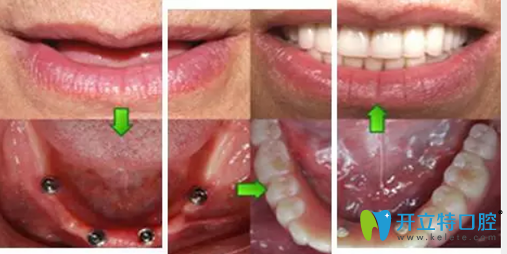

鎮(zhèn)江拜博口腔做All-on-4種植牙修復(fù)前照片:

鎮(zhèn)江拜博口腔做All-on-4種植牙修復(fù)前照片

All-on-4種植牙種植過程圖:

鎮(zhèn)江拜博口腔萬書健All-on-4種植牙種植過程圖

術(shù)后結(jié)束后,郭先生看著整齊的牙齒,笑得合不攏嘴,他說,有了牙,我就有了好胃口,胃口好了,我就能安心享受晚年的生活啦!